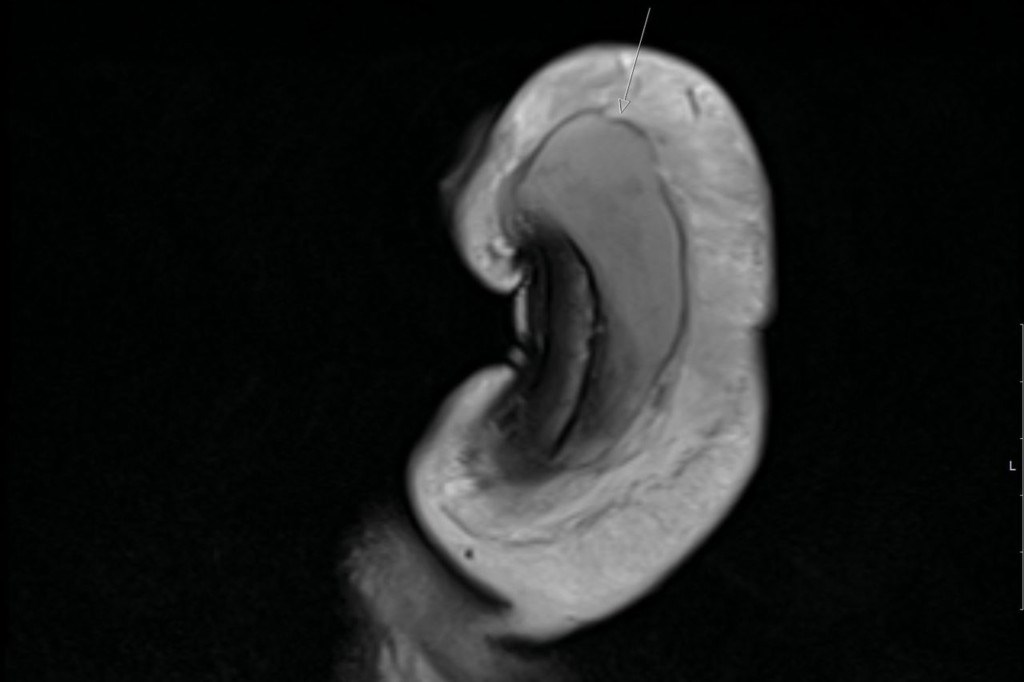

Είπαν ότι όλα τα κατάγματα του πέους που είχαν καταγραφεί στο παρελθόν ήταν οριζόντια. Αλλά σε αυτή την περίπτωση χωρίζει το tunica albuginea – το προστατευτικό στρώμα γύρω από τον στυτικό ιστό που αντλεί αίμα σε αυτήν την περιοχή. Ο γιατρός είπε ότι δεν ακούστηκε ήχος «αναδυόμενου» όταν συνέβη το σπάσιμο, το οποίο συμβαίνει όταν τα κατάγματα είναι οριζόντια. Τα σηραγγώδη σώματα συγκρατούνται από μια ισχυρή μεμβράνη που ονομάζεται ινώδης χιτώνας. Όταν ένας άνδρας υποφέρει από κάταγμα πέους, ουσιαστικά έχει σπάσει αυτή η ισχυρή μεμβράνη.

Όπως αναφέρει η Dailymail ο χαρακτηριστικός ήχος που ακούγεται στις περιπτώσεις σπασίματος δεν υπήρξε, επειδή αυτό συμβαίνει μόνο στις περιπτώσεις που είναι οριζόντιο το κάταγμα.